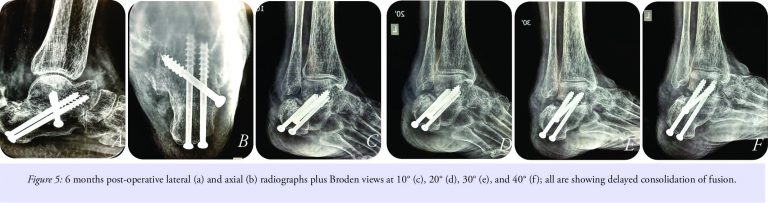

Teriparatide injections were added for enhancing union. X-rays at the end of 6 months did showed non-progressive and non-convincing progress of fusion (Fig. 5a-f).